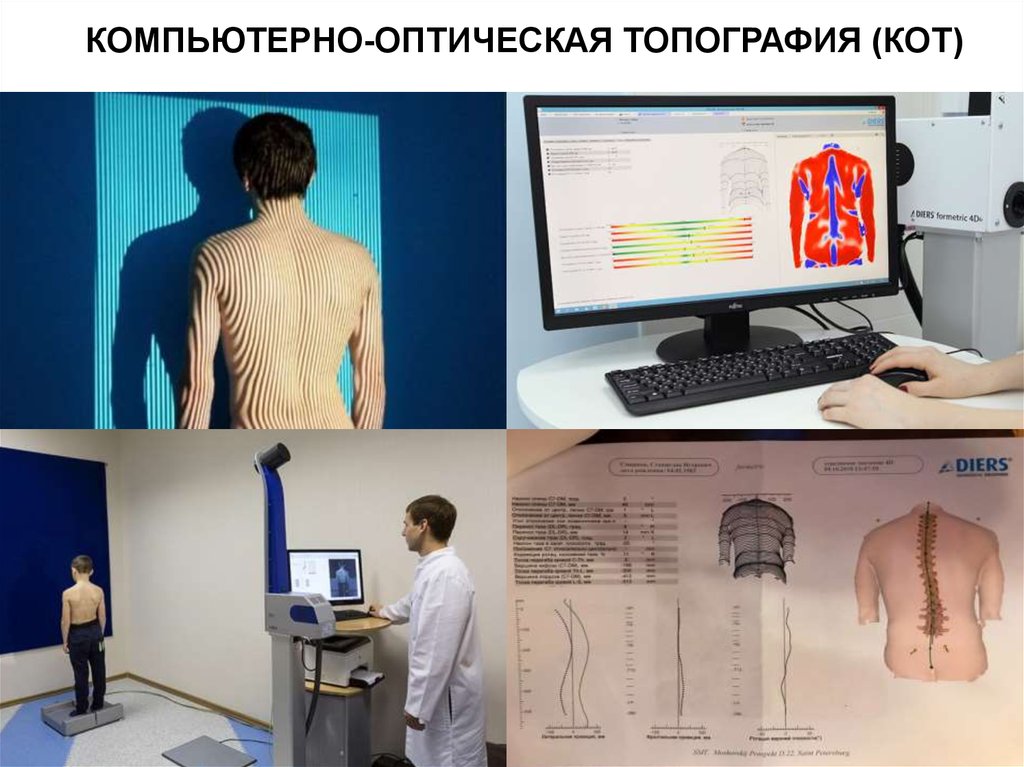

Оптическая диагностика позвоночника Diers: изображения и технологии

Раздел: Мир в картинках